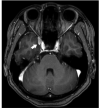

Figures